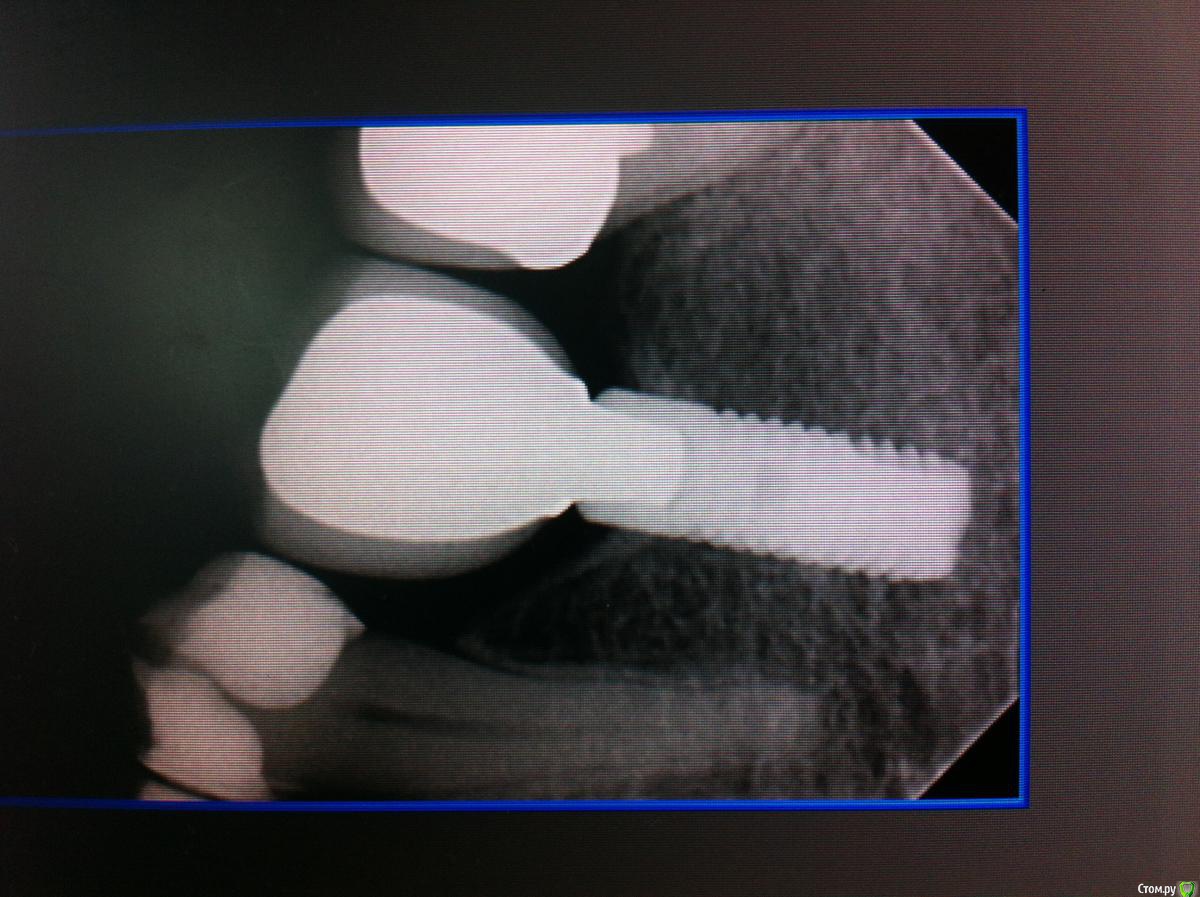

Айнур Фаязович Опубликовано 2 декабря, 2015 Поделиться Опубликовано 2 декабря, 2015 Пациентка обратилась с целью замены временной коронки на имплантате 36 на постоянную конструкцию. В ходе сбора анамнеза удалось выяснить, что 3 года назад у нее на 36 зубе произошла поломка винта внутри имплантата и, как следствие, появилась подвижность этой коронки. Ее доктору, у которого она протезировалась, удалось извлечь винт, но пришлось делать новую резьбу. Теперь она обратилась ко мне. Прилагаю фотографии полости рта, рентгеновские снимки до поломки винта, на момент обращения ( снимок с временной коронкой) и с трансфером для открытой ложки без винта (узкая платформа Астра). Дело в том, что у пациентки временная коронка на стандартном титановом абатменте ( платформа узкая 3,5-4,0) был зафиксирован с помощью винта от Dentium, при этом область шестигранника расширена изнутри ( чтобы проходил винт от Dentium) Но теперь возникают вопросы: 1)Как снять слепок с трансфером для узкой платформы, если родной винт не держится из-за изменения конфигурации резьбы, винт для широкой платформы и даже винт для Dentium слишком велики по размеру?2)Допустимо ли, по-вашему, менять конфигурацию постоянного абатмента в области шестигранника, расширяя его изнутри, чтобы проходил винт?3)Стоит ли проводить замену временной коронки на постоянную, если на рентгеновском снимке довольно серьезные повреждения в верхней части имплантата после изменения конфигурации резьбы. Уважаемые коллеги, если кто сталкивался с подобным, буду признателен за ваши варианты решений данной пробемы. За качество снимков прошу прощения, снимал на телефон. Ссылка на комментарий